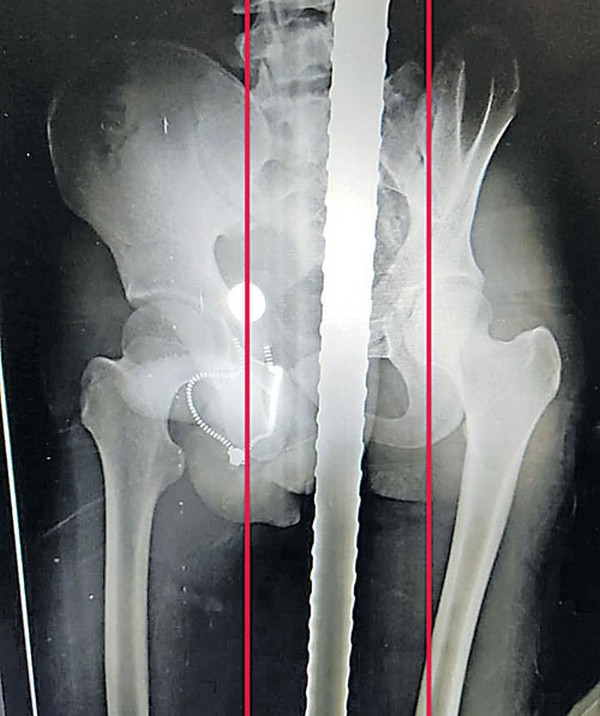

సువర్ణగిరి ప్రాంతానికి చెందిన సనాతన పటగురు అనే వ్యక్తి కుమారుడు శక్తి పటగురు. వయసు 16 యేళ్లు. శనివారం పాఠశాలకు వెళ్లాడు. తరగతి గదులపైకి ఎక్కి సిమెంట్ రేకులు తొలగిస్తుండగా, ఓ రేకు విరిగిపోయి కిందకు జారాడు. అదేసమయంలో అక్కడే ఓ కార్మికుడు గునపం పట్టుకుని వుండగా, కిందపడుతున్న బాలుడి మలంద్వారంలోకి సరిగ్గా చొచ్చుకునిపోయింది. దీంతో హుటాహుటిన సమీపంలోని ఆస్పత్రికి తరలించారు

గునపం తీసేందుకు అక్కడ సాధ్యపడక పోవడంతో ఎమ్కేసీజీ ప్రభుత్వ వైద్యశాళకు తీసుకెళ్లారు. ఆ ఆస్పత్రి వైద్యులు రాత్రి 8 గంటల నుంచి అర్థరాత్రి 12 గంటల వరకు శస్త్ర చికిత్స చేసి గునపాన్ని తొలగించారు. బాలుడి ఆరోగ్యం నిలకడగా ఉందని వైద్యులు చెప్పారు.